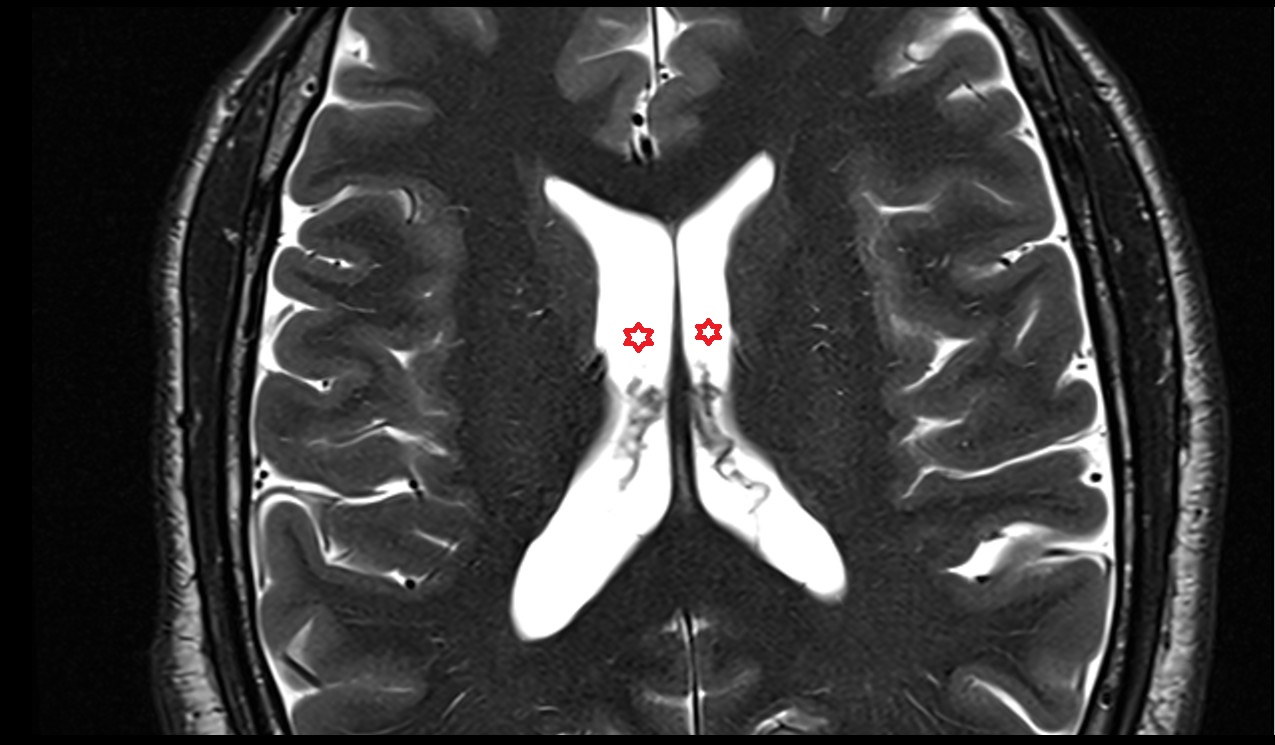

- Central part of lateral ventricle

- Frontal horn of lateral ventricle